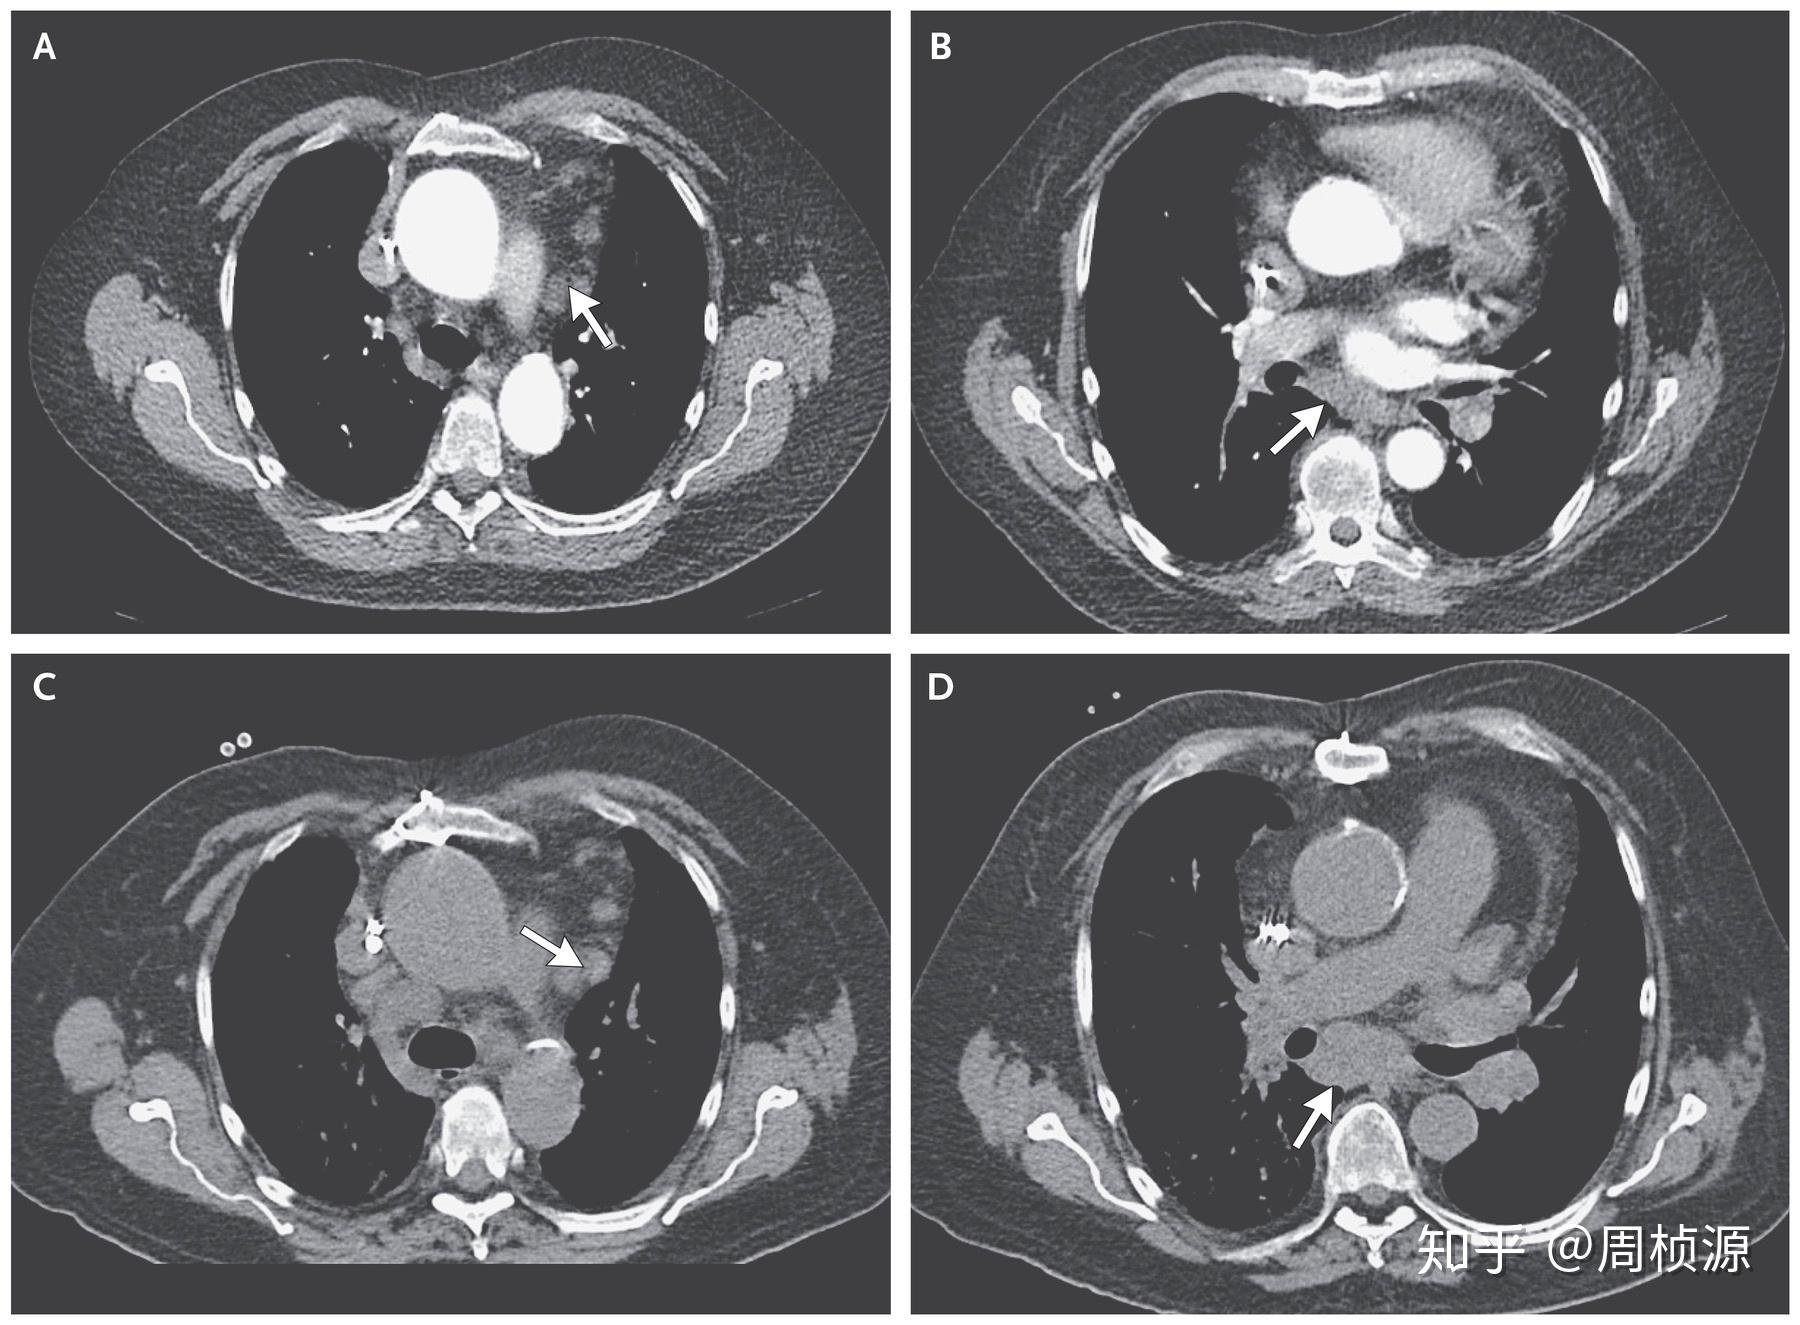

入院检查mpo-anca阳性,血尿蛋白尿,肺门及纵膈淋巴结肿大,肺底片状

影像学检查:胸片示左肺底大片浸润影,伴有纵隔气肿和散在软组织内气体

肺底混合磨玻璃结节,肺腺癌?